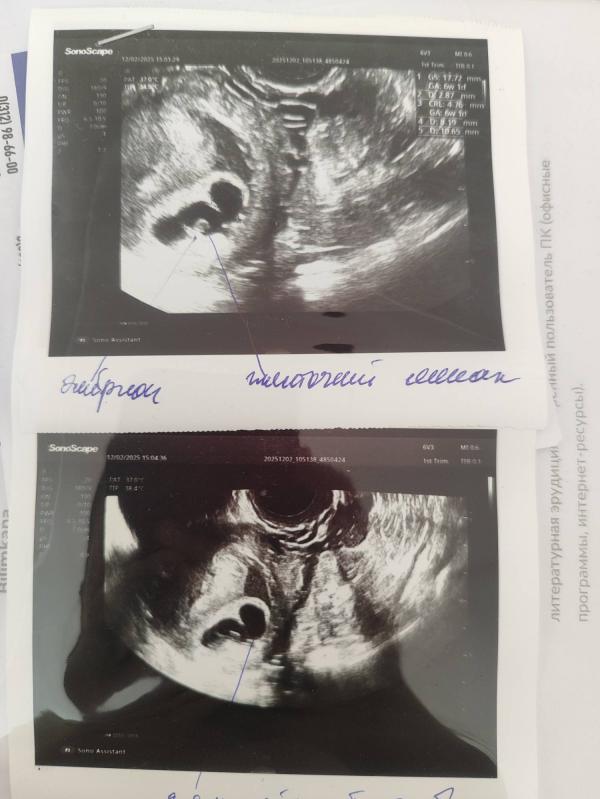

Сходила на первый УЗИ за эту беременность. Два плодных яйца, одно с эмбрионом, второе пустое. Оказывается так тоже бывает. Ещё с первым совпадали все сроки, а тут по календарю 7-8 недель, а по УЗИ 6. Стараюсь пока не паниковать, завтра на ХГЧ, через неделю УЗИ. Сказали, во втором уже никто не появится.